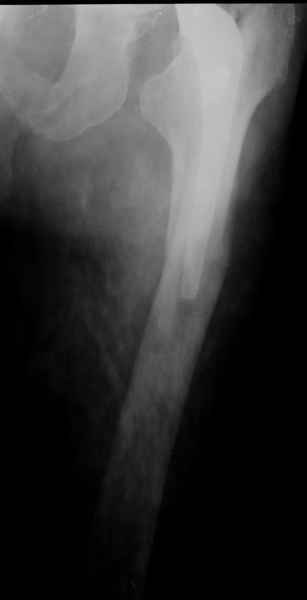

Весь проксимальный отдел бедренной кости ведь смещен относительно ножки эндопротеза? Значит менять ножку нужно. К тому же, если думать об удлинении ножки стержнем, место стыка получится как раз в области поперечной части перелома и о стабильности такой конструкции вряд ли можно будет думать. Так что - длинная ревизионная ножка с остеосинтезом. Может быть и серкляжей будет достаточно если перелом проксимальной части не оскольчатый (по снимкам не очень понятно).

ножка просела немного (вопрос, много - это сколько?)перечисленные проблемы - не самое важное сейчас, на них можно закрыть глаза. Ножка явно нестабильна, проксимальный отломок с б/вертелом к гвоздю не прицепить, срастется ли он с ножкой

Начинать, на мой взгляд, надо с того, что перелом-то произошел из-за порочной (варусной) позиции ножки, не случись он сейчас, это произошло бы еще через полгода при более невинных обстоятельствах. Не видел конструкций , но дизайн ножки сильно напоминает цементную стандартную ножку Мюллера и, стало быть, наверное есть цементная мантия. В любом случае, на реинтеграцию этой ножки расчитывать нельзя. Поэтому, если нет общесоматических противопоказаний, нужно выполнять ревизионное эндопротезирование, оптимальный вариант - ножка Wagner Cone.

Это"Corail", так что никакой цементной мантии там нет.Непонятно с чего Вы решили,что ножка была установлена в "варусе"? Нынешнее ее положение, получено после травмы.

Частично правильный ответ - 1. Это В-2 перелом (проксимальный отдел скорее жив, чем мертв). Костная пластика кортикальными трансплантатами необходима. Также необходим остеосинтез большим количеством проволочных металлических серкляжей. Пластина не нужна.

Используя ножку "Вагнер", как советует Рашид Муртазалиевич получите хорошую фиксацию по каналу, качественную адаптацию отломков, экономию финансов.